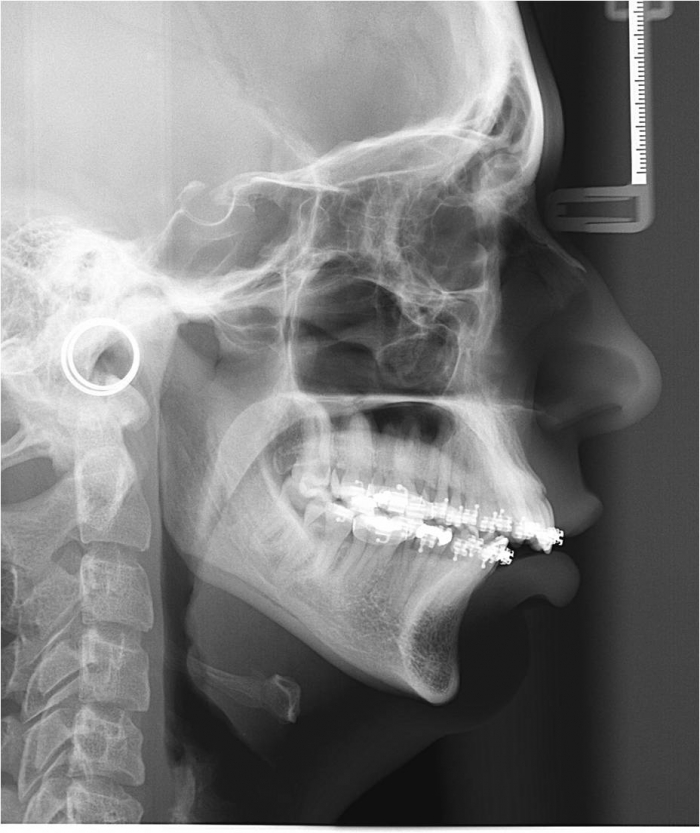

Telerradiografia após a cirurgia